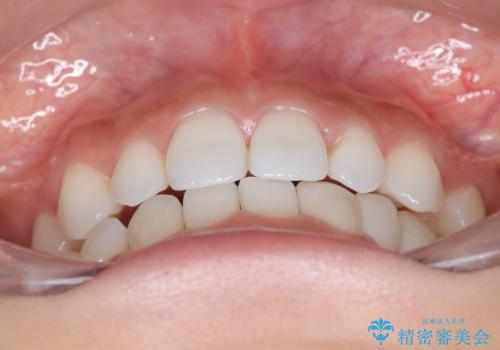

- 空隙歯列を主訴に来院された患者様です。

ばらけている空隙を一箇所に集めながら咬合や正中を改善して最後に補綴治療を行なっています。

右上の臼歯クロスバイトは骨格生のため、そのままにしています。